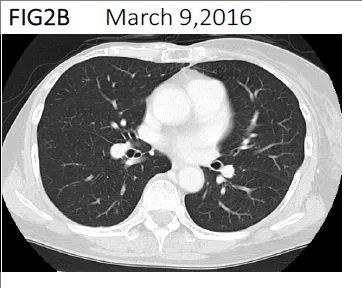

▼2016年3月计算机断层扫描

注:影像学显示,胸腔积液完全消失。